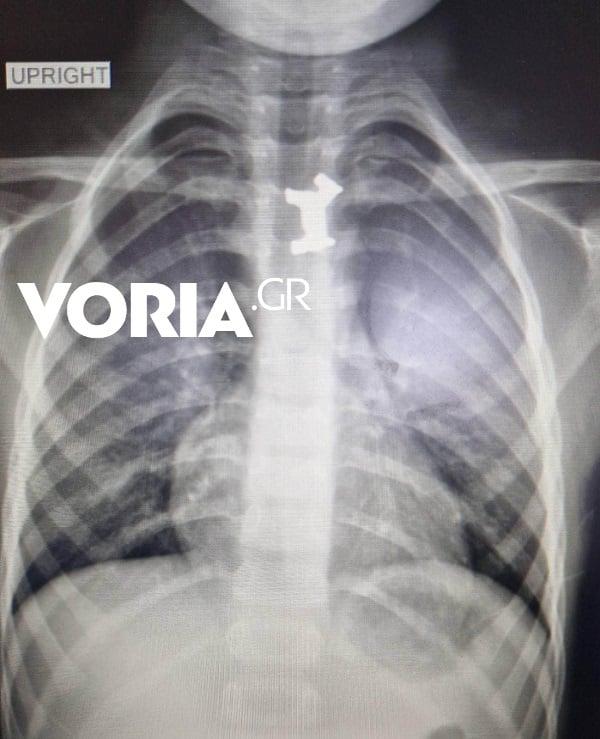

Σύμφωνα με πληροφορίες της ιστοσελίδας Voria, μετά από τις ακτινογραφίες και τις απεικονιστικές εξετάσεις διαπιστώθηκε πως το παιδί είχε καταπιεί ένα μεταλλικό πιόνι από γνωστό επιτραπέζιο παιχνίδι που έπρεπε να αφαιρεθεί άμεσα, καθώς ήταν σε αρκετά δύσκολο σημείο.

Αφότου έγιναν όλες οι απαραίτητες εξετάσεις για τον ακριβή εντοπισμό του αντικειμένου, αλλά και μετά από εκτίμηση των γιατρών υπεβλήθη σήμερα το πρωί σε οισοφαγοσκόπηση -πρόκειται για μέθοδο αντιμετώπισης οξέων αποφράξεων του ανώτερου πεπτικού στα παιδιά- υπό γενική αναισθησία για την αφαίρεσή του από τον οισοφάγο.

Χαρακτηριστικές είναι οι φωτογραφίες που δείχνουν το σημείο όπου σταμάτησε το μεταλλικό αντικείμενο στον οισοφάγο του παιδιού: